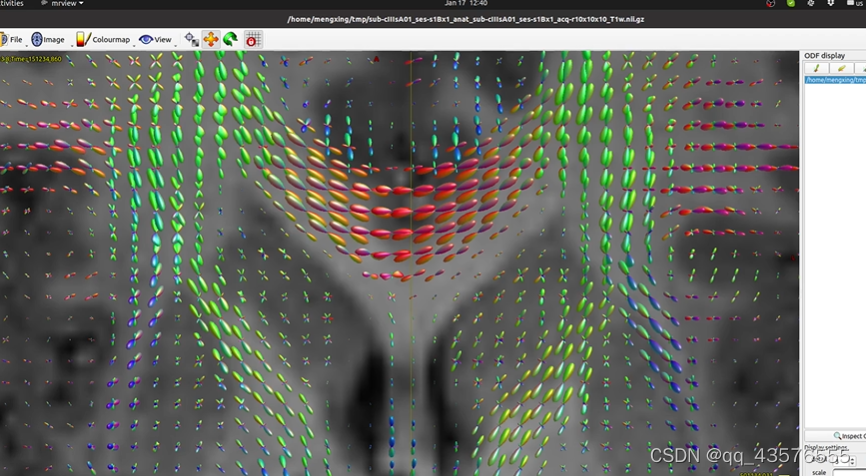

maskfilter: [100%] applying dilate filter to image -生成弥散张量dt.mif,可用mrview查看,每个体素有六个值(描述一个椭圆体),标志着水分子的弥散方向,用椭球方向标志纤维的走向,用FA值衡量各向异性,各向异性越大,FA值越大

tensor2metric: [100%] computing metrics由于弥散像体素比纤维大得多,无法反映神经纤维束的真实走向,这里我们不用dt.mif估算神经的方向,因此使用constrained spherical deconvolution(CSD)算法,计算各个方向纤维束的贡献,这里的kernel称为反应函数

dwi2response: Deleting scratch directory (/home/hzhb/Fengz/demo/dwi2response-tmp-MWHD2Y/)得到反应函数后,我们估算FOD,该步骤大概需要几分钟,可以用mrview查看得到的文件dwi_gmCsd.mif等,得到每个体素的不同纤维走向的贡献程度(可能性大小)